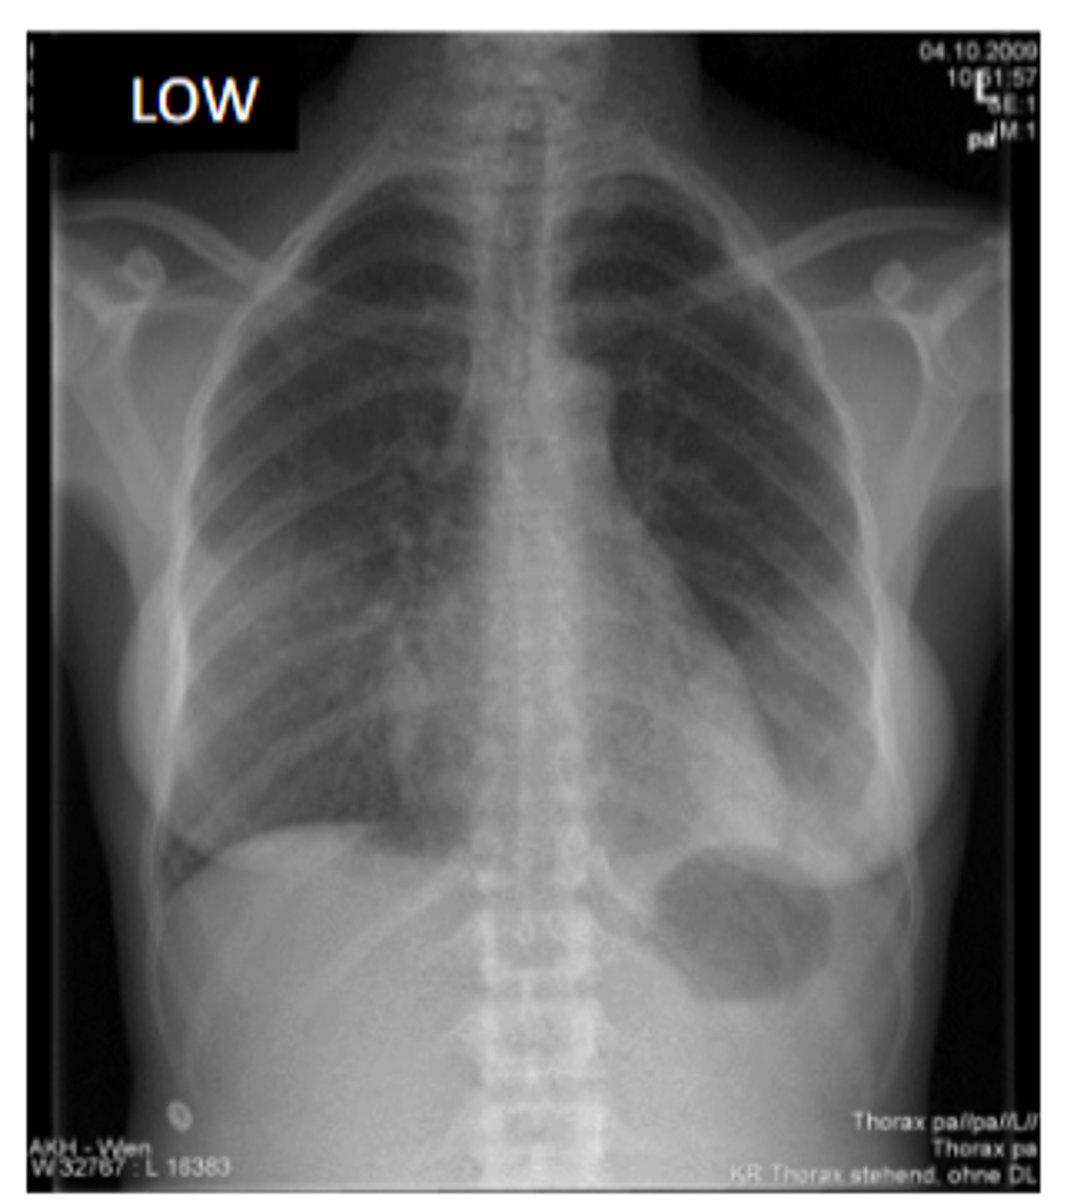

for a chest xray what kind of view will they take

PA

because you want the heart furthest away from the xray beam and closer to the IR

during a chest xray what kind of contrast should you use to view soft tissue

low

true or false you can use a chest xray to view lungs, vascular system and metastatic disease

true